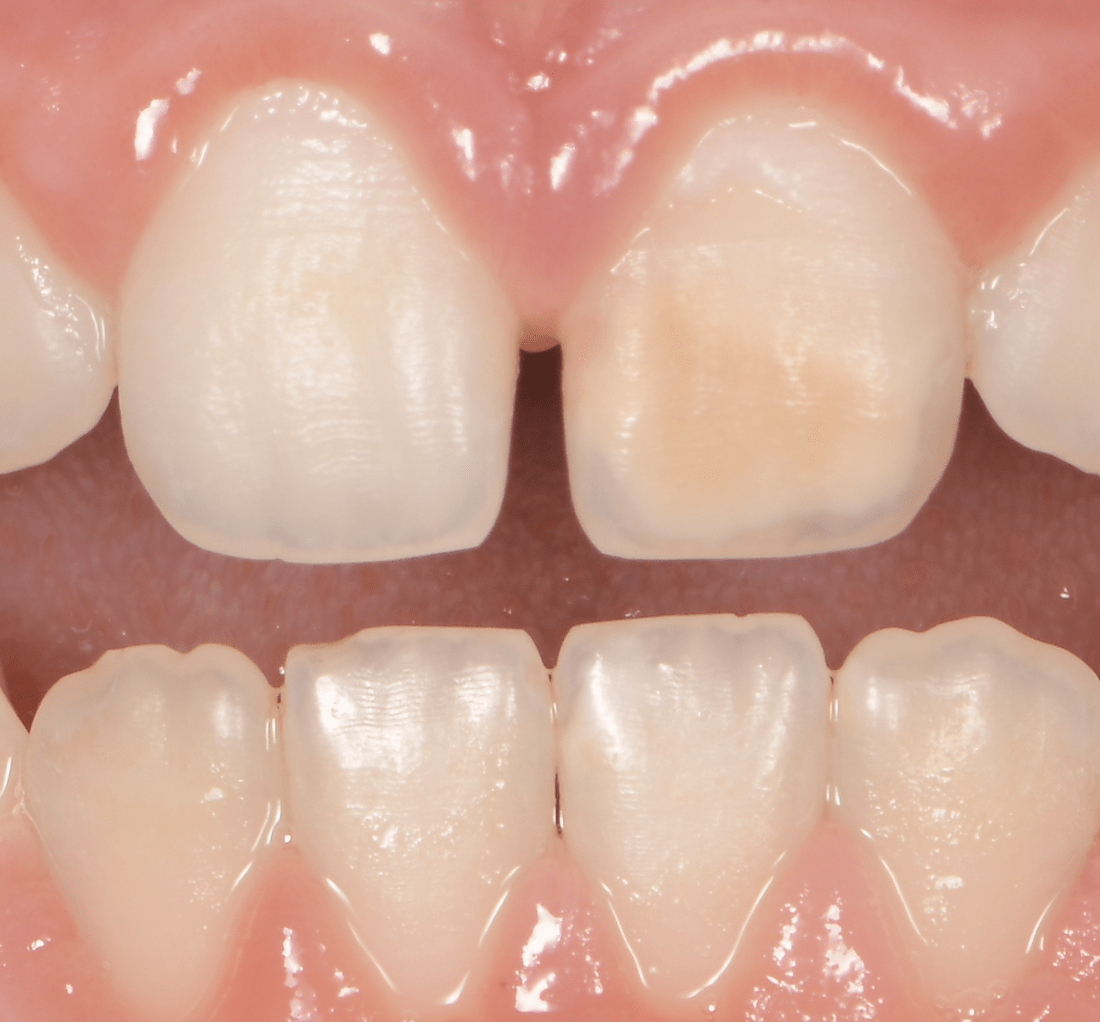

Si en antérieur, le préjudice esthétique n’est pas trop important et qu’il n’y a pas de perte de substance, il est conseillé d’attendre la majorité afin de réaliser un éclaircissement suivi de la technique d’érosion infiltration (ICON), plus ou moins une stratification de composite esthétique (Figures 8-9-10).

formation dentaire pédodontie Figure 8.

formation dentaire pédodontie Figure 9.

formation dentaire pédodontie Figure 10.

Figures 8-9-10 : Traitement antérieur, éclaicissemet bouche complète, ICON et stratification de

composite sur 11 (l’éclaircissement ayant suffit pour la 41)